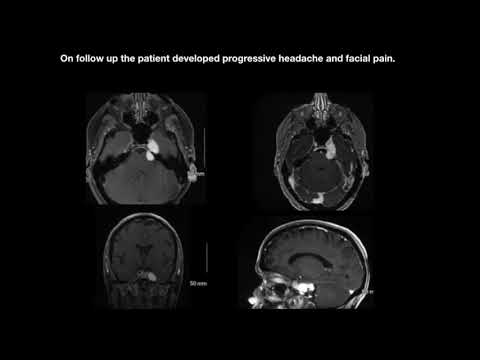

Hellow guys, Welcome to my website, and you are watching Anterior Petrosal Drilling - Planning and Technique. and this vIdeo is uploaded by NETS AIIMS at 2014-10-08T00:20:01-07:00. We are pramote this video only for entertainment and educational perpose only. So, I hop you like our website.